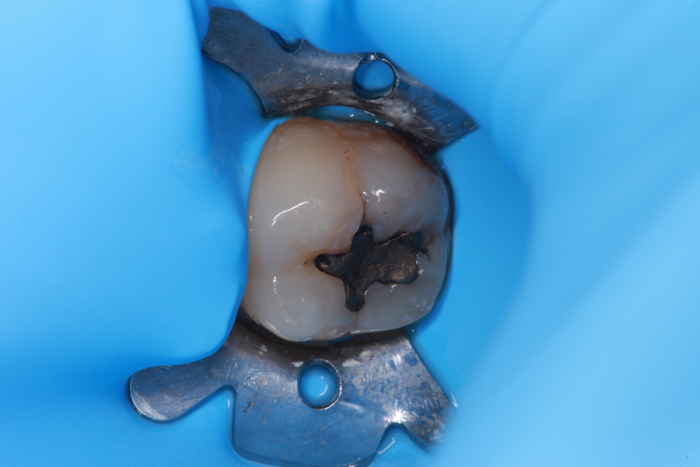

Technically, the procedure was very efficient. After the placement of rubber dam, the amalgam restorations (Fig. 1) and any signs of caries were removed (Fig. 2).

Fig. 1: Failed amalgam restoration. Fig. 2: Amalgam and decay are removed and tooth is prepared with ACTIVA BioACTIVE-RESTORATIVE.